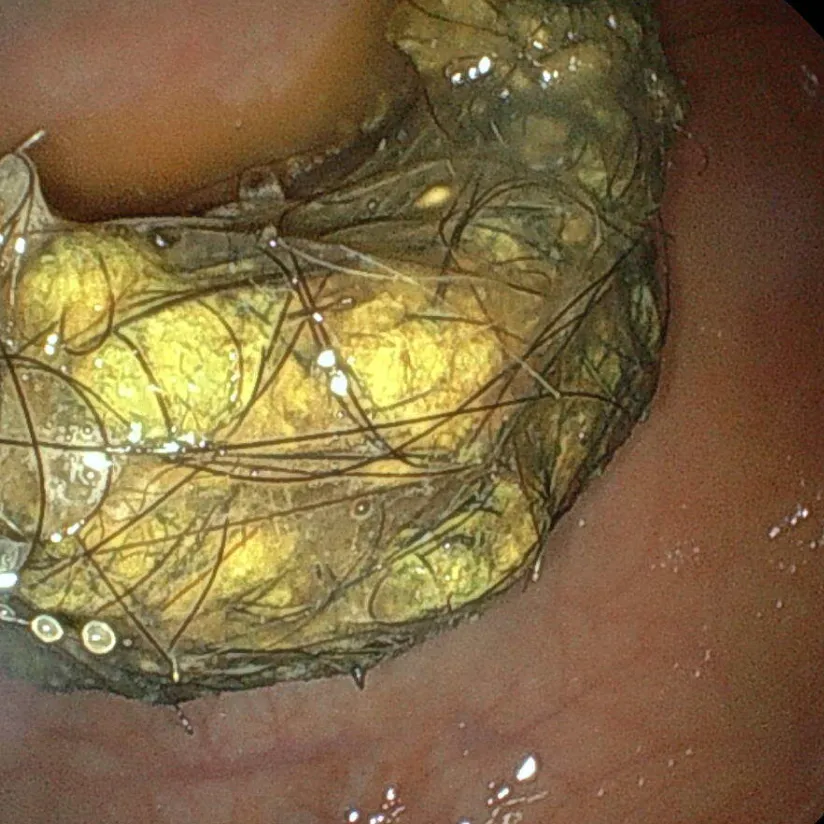

慢性腸症が疑われるが試験的治療で改善しない場合は内視鏡検査を実施し、生検を行うことで初めて診断を確定することが可能となります。

試験的治療が奏功しなかった慢性腸症の場合には、内視鏡検査で病気を確定診断した上でステロイド治療などの治療強化に移行していきます。

消化管型リンパ腫は胃腸にできる癌の一つで、リンパ球という免疫炎症細胞が癌化した悪性腫瘍です。悪性度・分類・発生部位・動物種(犬猫)により治療方法や予後は異なります。また、好発犬種(柴犬、パグ)も報告されています。消化管型リンパ腫は患者さんごとに症状や病変の現れ方が異なるほか、悪性度の低い消化管型リンパ腫は良性の慢性腸症と症状も一般検査の所見も酷似するため確定診断のための内視鏡生検が推奨されます。治療には抗がん剤治療が適応ですが、病態によっては外科手術+抗がん剤治療となることもあります。ベネフィット(治療効果)とリスク(抗がん剤の副作用など)を十分にご理解いただいた上で治療方針を決めていきます。

内視鏡は患者の体に大きな傷を付けずに、胃腸内の状態を確認するための機器です。

小型カメラを用いた目視での病変確認のほか、組織の一部を採取し専門的な検査を行うことで病気を特定することができ、その後の治療を円滑に進めることができます。また、観察や生検といった検査ツールだけでなく、ポリープ切除・栄養チューブ設置といった治療ツールとしても活躍します。

一方で内視鏡の効果を最大化させるためには獣医師の卓越した技術が必要です。事実、内視鏡は操作技術がないと観察できる範囲が限られてしまうほか、採取した組織の質次第でその後の診断の病気検出率に差が出ることが論文で示唆されています。

当院では最新の内視鏡機器を導入しています。また、施術には二次診療施設で消化器科を専門とし、毎日のように豊富な内視鏡経験を積んだ獣医師が施術にあたり、質の高い獣医療をご提供します。